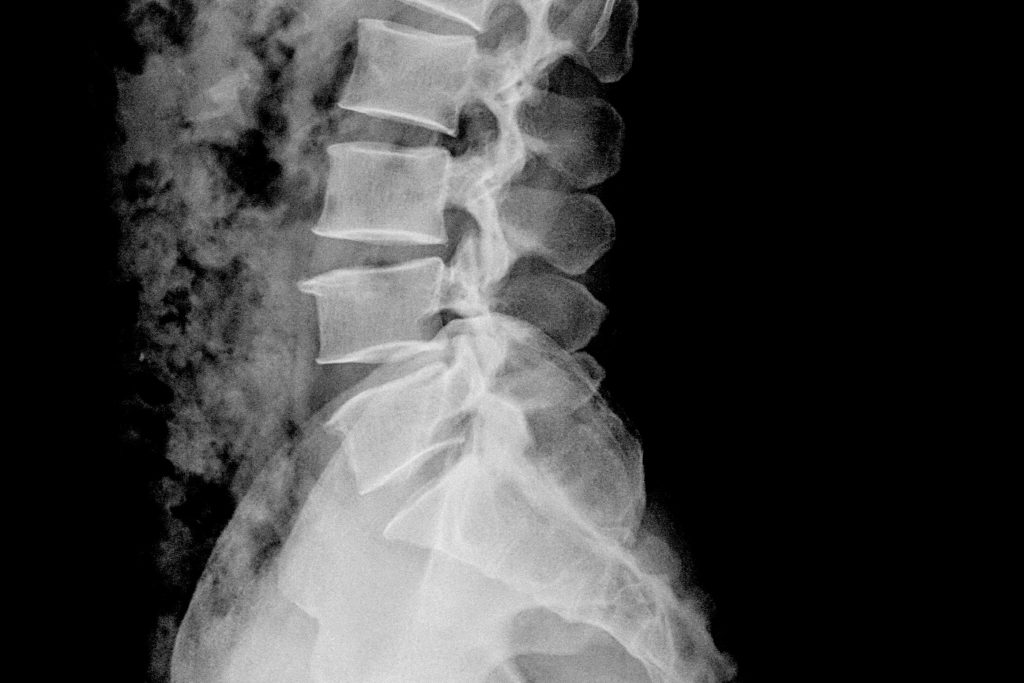

The role of medical imaging in diagnosing back pain.

X ray or mri for back pain. The difficulty with the results of an mri scan, as with many other diagnostic studies, is that the abnormality that shows up on the mri scan may not actually be the cause of back pain. Each offers important clues to the underlying causes of back pain, and each plays a. Would it be helpful to do an mri or any other type of scan? answered by dr.

That depends on the ordering physician, better see a spine spe. Lower back pain (lbp) is one of the most common chief complaints encountered in primary care. Spinal abnormalities, such as herniated discs, are frequently diagnosed using medical imaging.

Advanced imaging studies, including computerized tomography (ct) and magnetic resonance imaging (mri), are frequently ordered in the setting of lbp. Those in one muscle can affect all the rest of the muscles and begin to cause pain. Publish your next review or original research paper with molecular imaging.

1 2 mri can shine when it’s actually needed and done well. Even though mri(magnetic resonance imaging) is considered a “gold standard” in evaluating spinal problems it is not perfect. The human body is an amazingly complex organism that is constantly changing and adapting or our activities or inactivity.